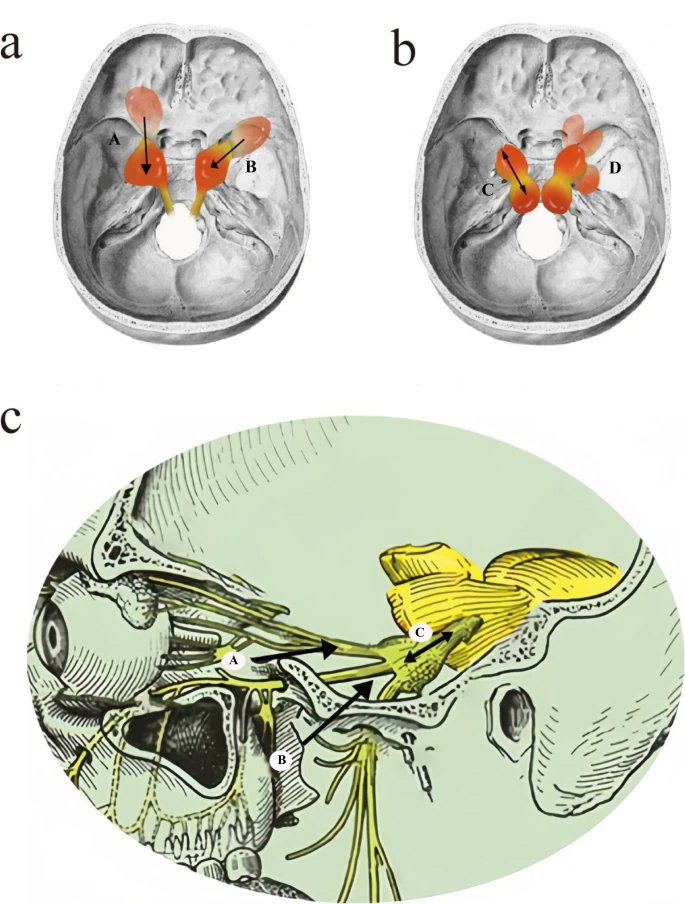

#Cadaveric image of the #trigeminal nerve branches arising from the trigeminal (#Gasserian) ganglion, extending into the orbit, the pterygopalatine & infratemporal fossae. journals.lww.com/contempneurosu… #nsgy #education #skullbase #neurosurgery #neuroanatomy #microsurgery #neurosurgeon

DrBaskaya's tweet image. #Cadaveric image of the #trigeminal nerve branches arising from the trigeminal (#Gasserian) ganglion, extending into the orbit, the pterygopalatine & infratemporal fossae.